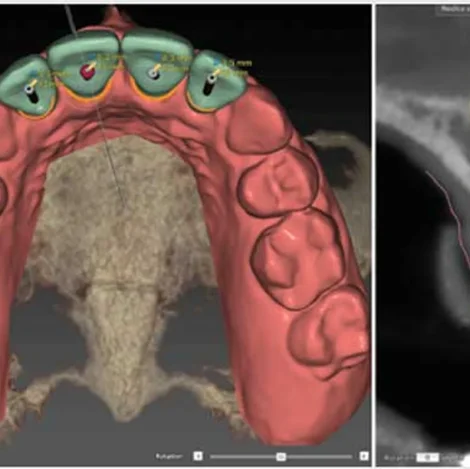

Implantologia Guidata: chirurgia mini-invasiva di alta precisione.